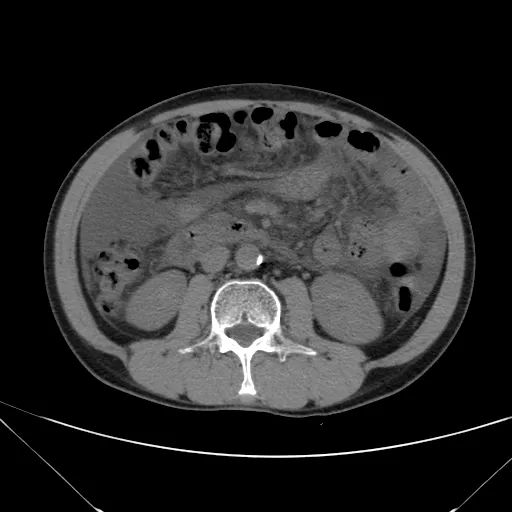

除了观察肝硬化相关表现外,还应根据看片顺序继续观察胆囊 胰腺 脾脏 泌尿及生殖系统,最后别忘记主动脉及周围腹膜后结构,骨质及肌肉。

肝脏缩小,包膜凹凸不平,肝裂增宽,各叶比例失衡,肝实质密度不均,肝S4小片低密度影,约cm;胆囊不大,其内未见异常密度影,胆道系统未见扩张;胰腺、脾脏形态、密度、大小未见异常;双肾上腺及双肾形态、密度、大小未见异常,双输尿管未见扩张,膀胱充盈良好,壁光滑,其内未见异常密度影;前列腺未见异常;胃肠道未见充盈,壁未见明确增厚,食管胃底多发迂曲、增粗血管,腹部及腹膜后未见肿大淋巴结;腹水。